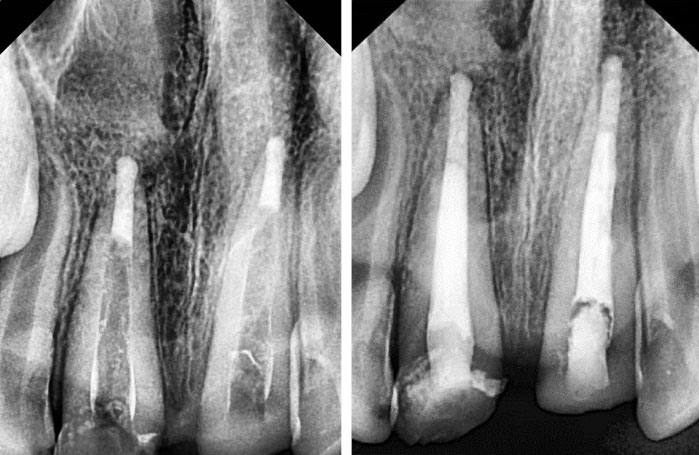

A 10-year-old boy referred to the Department of Pediatric Dentistry of Hamadan University of Medical Sciences. The chief complaints of the patient were pain and fractures of anterior teeth (Figure 1). According to his parent’s report, he had a motorcycle accident two month ago. Medical history and extraoral examination were normal. A form of informed consent was signed by parents for performing treatment procedure and presenting case report in the future. In clinical and radiographic examinations, there were no maxillary and mandibular fractures. The patient had class II malocclusion with deep bite (Figure 2). Intraoral periapical radiography revealed partial loss of the crown and oblique crown root fracture of teeth 21 and 11. The development of root apex of teeth 21 and 11 was incomplete (Figure 3). Vitality pulp tests were performed and the teeth responded negatively to electrical and thermal tests. Due to the incomplete development of roots and the time elapsed since the injury, the prescribed treatment plan was the apexification of teeth with MTA plug (Figure 4). After pulp therapy, temporary restoration was applied to the teeth 21 and 11. After multidisciplinary consultation with Pediatric Orthodontics and Periodontology departments, it was decided that a surgical extrusion was the best way to expose the fracture line. Surgical extrusion was performed for definitive treatment and reconstruction of the coronal segment because the palatal portion of the fracture line continued down to the gingival margin and was approximately 1 mm below the alveolar crest. By a periosteal elevator and a sharp carver, the teeth were gently luxated. The teeth were extruded about 4 mm by forceps which took the mesiodistal of the tooth. Due to tooth mobility at this stage, fixation in the new position was performed by a wire-composite splint (wire diameter: 0.6 m) (Figure 5). Proper antibiotic therapy was prescribed for the patient for 10 days. The patient and his parents were informed about the importance of oral hygiene and soft diet during the healing period. After two weeks, the splint was removed and the tooth mobility significantly reduced (grade I). Then, temporary tooth restoration was removed and the fiber optic post was prepared and cemented with dual-cure resin. Finally, a composite build-up was performed for maximal aesthetic outcomes (Figure 6). During the follow-up period of 2 years, no trace of root resorption was observed (Figure 7). The patient referred to the Department of Orthodontics for orthodontic treatment.

Figure 3.

Pre-operative Periapical Radiography of Teeth 21 and 11.

Figure 4.

Post-operative Periapical Radiography of Teeth 21 and 11 After Apexification.